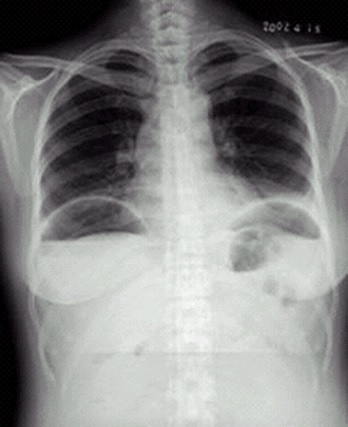

04卷-4.病史:女性,42岁,腹痛1天,进行性加重。诊断

A.肠梗阻

B.肠结核

C.正常腹平片

D.消化道穿孔

题目解析:【该题针对“ X线-消化道穿孔 ”知识点进行考核】